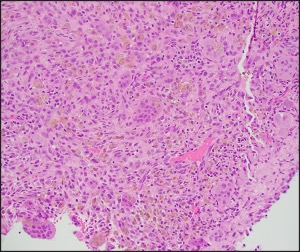

Histologic Findings

H&E stained sections demonstrated thin fibrous septa.

The septa comprised of fibrous stroma with spindled cells, osteoclastic giant cells, lymphohistiocytic inflammatory cells, extravasated red blood cells, and scattered hemosiderin deposits.

Focal solid areas are seen.

Reactive bone formation and dystrophic calcification were occasionally seen.